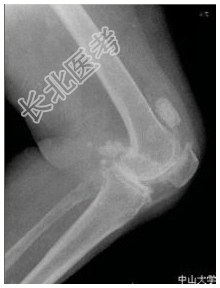

- [材料题] 患者女,55岁,双膝隐痛十余年。查体:双膝压痛,局部软组织肿胀,触之硬物感。行双膝关节正侧位片检查。

- 简答题1、患者的诊断及依据是什么?

- 简答题2、鉴别诊断是什么?